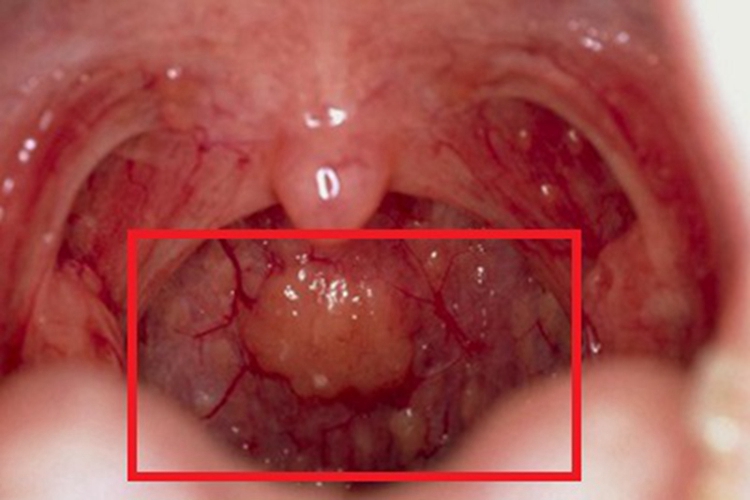

- 长期持续的咽炎会不断刺激咽部的组织,在反复刺激之下,咽部组织容易出现异常增生和肥厚,不仅会让咽部的异物感更加强烈,使人总感觉有东西堵在咽部,而且还可能对正常的吞咽动作造成阻碍,影响营养的摄入和身体的正常代谢。